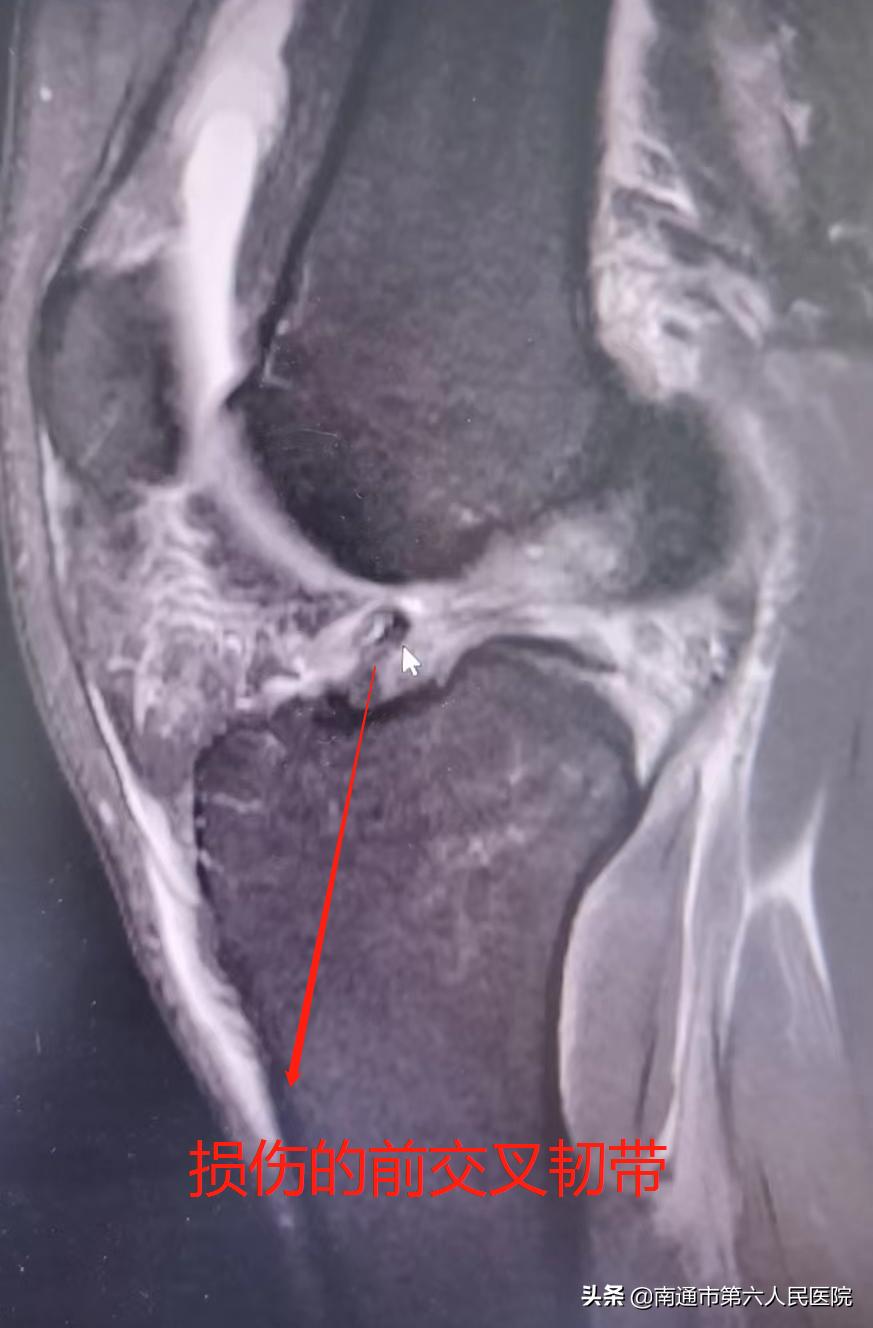

近日,28岁的小吴与好友在篮球场上做对抗时膝关节受伤,活动受限,一查竟是膝关节前交叉韧带断裂。

“本来绕过对方后转身起跳,想来一个漂亮的投篮,结果被人撞飞,落地时不稳,就听到膝关节‘啪’的一声,直接就站不住了,钻心地疼,膝盖瞬间肿起来了。”受伤后,小吴立即前往南通六院(上大附院),急诊检查发现竟是膝关节前交叉韧带断裂。“以后别说打球,估计我这条腿要残废了!”小吴焦急万分。

“膝关节前交叉韧带断裂,在日常生活和运动中比较常见,急停、转身、瞬间变向、落地不当等情况下更加容易发生,还常常伴有内侧副韧带以及半月板不同程度的损伤。”南通六院副院长、关节外科主任邓建华介绍,前交叉韧带是膝关节四大韧带结构的核心,也是最容易损伤的韧带之一。

前交叉韧带断裂,就如同凳子断了一条前腿,无法再维持膝关节的前向稳定性。对于明确诊断的韧带断裂患者,如果未能得到及时有效治疗,恢复膝关节稳定性,半月板、关节软骨容易出现继发损伤,进而发展为创伤性骨性关节炎,膝关节会反复疼痛,活动必然受限,日常生活都会受影响,更不用说打篮球了。